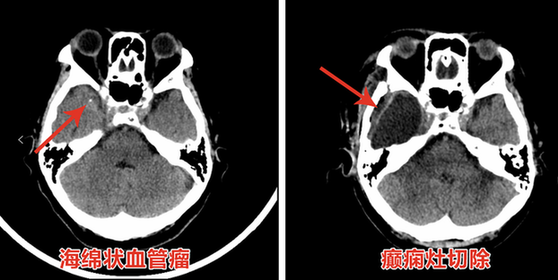

日前,首都醫科大學三博腦科醫院癲癇中心外科主任、主任醫師周健,為70歲的吳阿姨成功切除致癲灶——顱內海綿狀血管瘤,術後,影響吳阿姨20年的癲癇未再發作,恢復良好。

手術如期舉行。透過先進的技術手段對病灶進行定位。在精準導航下,主刀醫生周健主任抽絲剝繭,直至全部切除顱內海綿狀血管瘤,同時將病變組織連同致癇灶一併切除。清除完成後,監測發現癇性波消失。手術順利結束,這意味著患者將擺脫癲癇發作的痛苦。